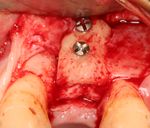

An incision is made across the area and the flap of gingiva is opened to show the bone of the jaw.

An incision is made across the gingiva, and the flap of tissue is reflected to show the bone of the jaw.

A series of slow-speed drills create and gradually enlarge a site in the jaw for the implant to be placed. The hole is called an osteotomy.

Once the bone is exposed, a series of drills create and gradually enlarge a site (called an osteotomy) for the implant to be placed.

The implant fixture is turned into the osteotomy. Ideally, it is completely covered by bone and has no movement within the bone.

A healing abutment is attached to the implant fixture and the gingiva flap is sutured around the healing abutment.

A healing abutment is attached to the implant fixture, and the flap of gingiva is sutured around the healing abutment.